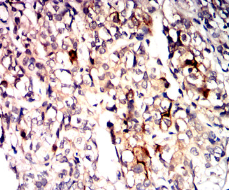

IHC    1/200 - 1/1000